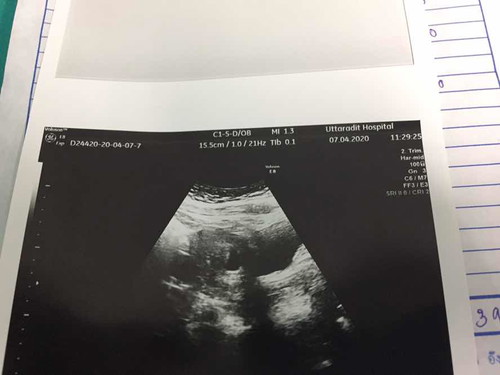

ดูไม่ออกเลยค่ะไปซาวท้องมา

แม่ๆช่วยกันดูหน่อยได้มั้ยค่ะ ส่วนไหนหัว ส่วนไหนตัว งงมากค่ะ??

บ้านนี้ซาวรอบแรกตอน14wมองไม่ออก รอบสองตอน18w. เริ่มดูออก รอบสามซาว4มิติ28w. ชัดแจ๋วคะ แม่อาจจะอายุครรภ์ยังน้อยหรือเปล่าคะ

ดูยากค่ะคุณแม่ มีภาพอื่นๆด้วยมั้ยคะ

อายุครรภ์น้อยรึเปล่าคะคุณแม่

ดูไม่ออกเหมือนกันค่ะแม่